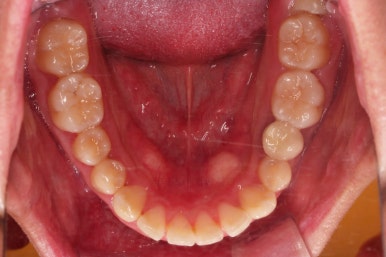

초진 시 입안의 모습입니다.

부정교합이 있고요.

또한 눈에 띄는 모습은 앞니가 튀어나오고, 사이사이 틈새가 보인다는 점이에요.

치열이 매우 가지런해졌고 틈새도 없어졌으며 교합도 잘 맞아졌어요.

사이가 다시 벌어지거나 틀어지지 말라고 치아 안쪽면으로 부착형 철사 유지장치를 붙이고 마무리를 했어요.